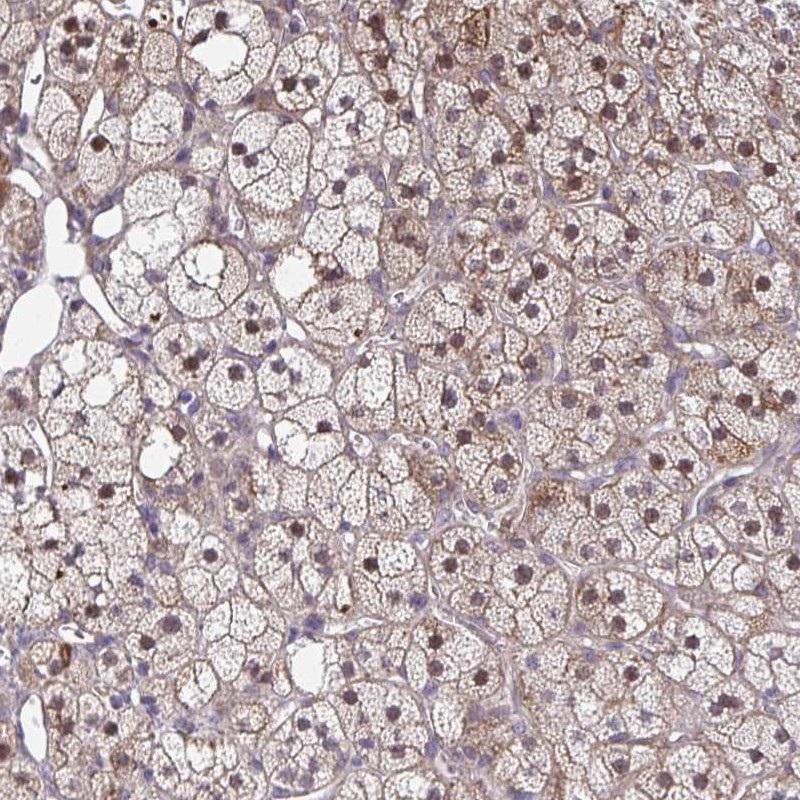

Immunohistochemical staining of human adrenal gland shows nuclear and cytoplasmic positivity in glandular cells.